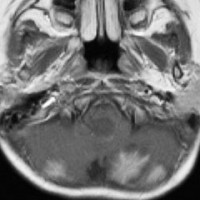

乳児の髄芽腫の治療後の硬膜血管腫

生後8ヶ月で髄芽腫を発症して,手術後に8コースの化学療法して,残存腫瘍があったために2歳半で脳脊髄照射18グレイと後頭窩局所照射21.6グレイをしました。放射線治療後2年で見つかった左前頭部腫瘍です。てっきり脳表播種再発かと思いましたが,良性の硬膜血管腫でした。この子は20歳となり再発もなく元気です。幼児期の放射線治療あるいは化学療法は,予想より早期に,珍しい2次腫瘍を誘発することがあると考えたほうがいいのでしょう。この腫瘍の部位には1日線量1.8グレイで18グレイしか照射されていませんでした。